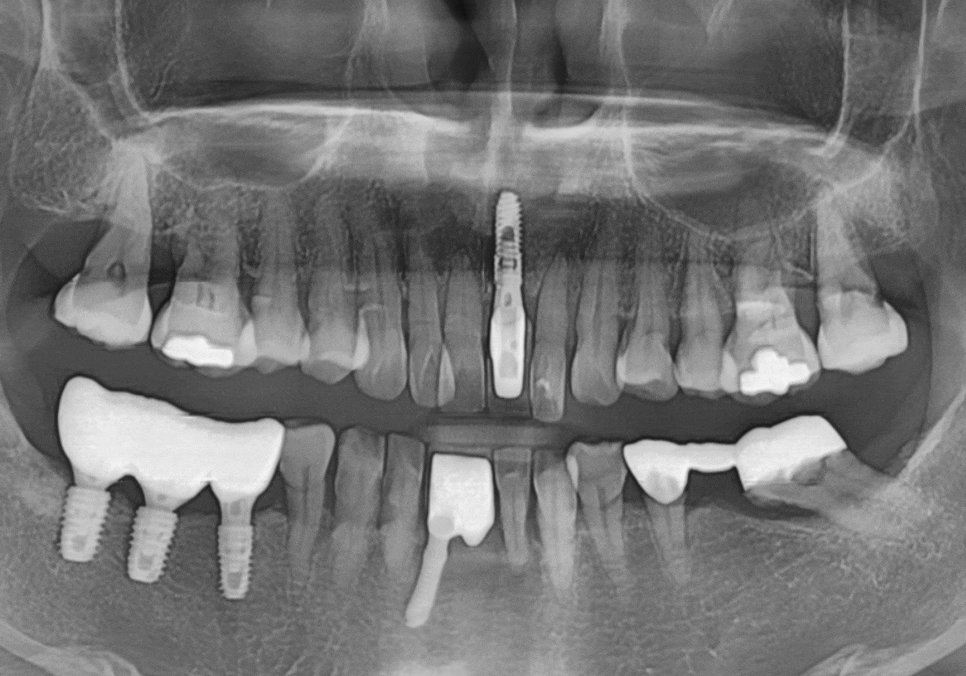

방사선 사진상,

치아 뿌리끝 염증도 진행되었고

뼈가 녹아 흔들림도 있던 상태라

231107 뿌리 끝 염증으로 뼈가 녹은 모습

방사선 사진상, 뿌리끝 염증으로

뼈가 녹은 부위가 있었고,

뼈 폭도 얇아 임플란트만 식립하기엔

무리가 있어 보였습니다.

그래서 저는 CT로 뼈 두께와

뼈 상태를 먼저 확인하고,

컴퓨터로 모의수술(가상 수술 계획)을 진행합니다.